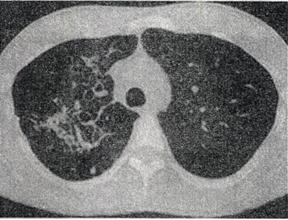

患者男,25岁,咳嗽,咯血近1周,午后低热1个月余,CT检查如图。如图所示,患者左侧肺部为何种基本病变

- A.肺脓肿

- B.钙化

- C.增殖性病变

- D.空洞

- E.积液

-

根据影像学表现,该病最应该与下面哪种疾病鉴别

- A.畸胎瘤

- B.肺结核

- C.肺脓肿

- D.支气管扩张

- E.肺大疱

根据患者病史及CT表现,最可能的诊断是

- B.双上肺结核

- C.液气胸

- D.肺大疱

- E.肺炎